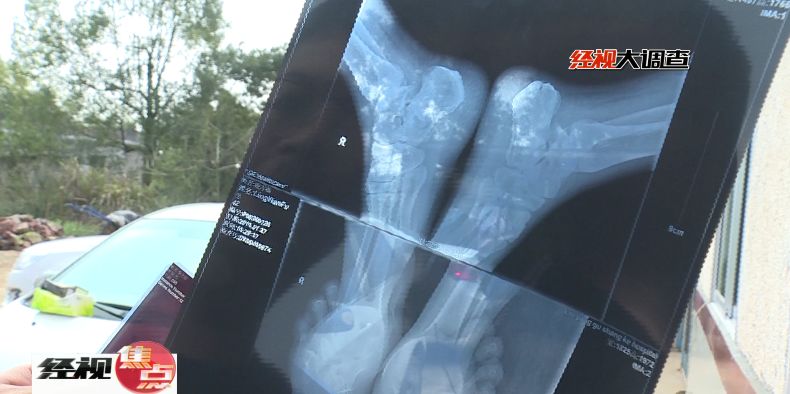

瀏陽市骨傷科醫(yī)院骨傷科醫(yī)師向吉告訴記者,患者左腳右腳腳后跟都摔斷了,從片子上看得到雙跟骨粉碎性骨折,當(dāng)時(shí)要立即進(jìn)行手術(shù),如果不做手術(shù)患者以后站立都有問題。

醫(yī)院很快安排了手術(shù),一個(gè)半月后患者才出院回家休養(yǎng)。此次意外受傷造成患者雙跟骨粉碎性骨折,意味著患者至少半年里要坐在輪椅上。